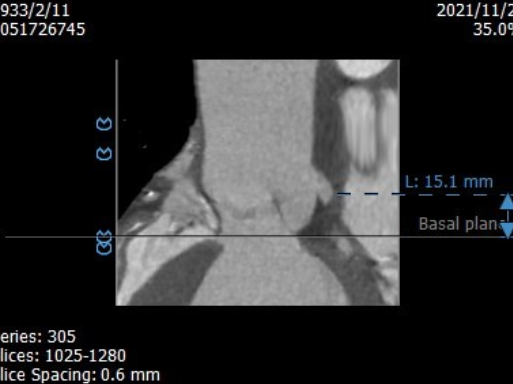

术前CT评估:

左冠高度15.1mm

右冠高度22.8mm